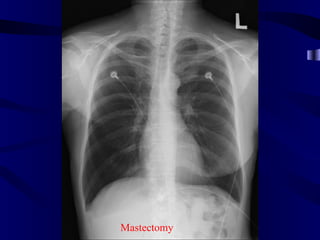

Mastectomy